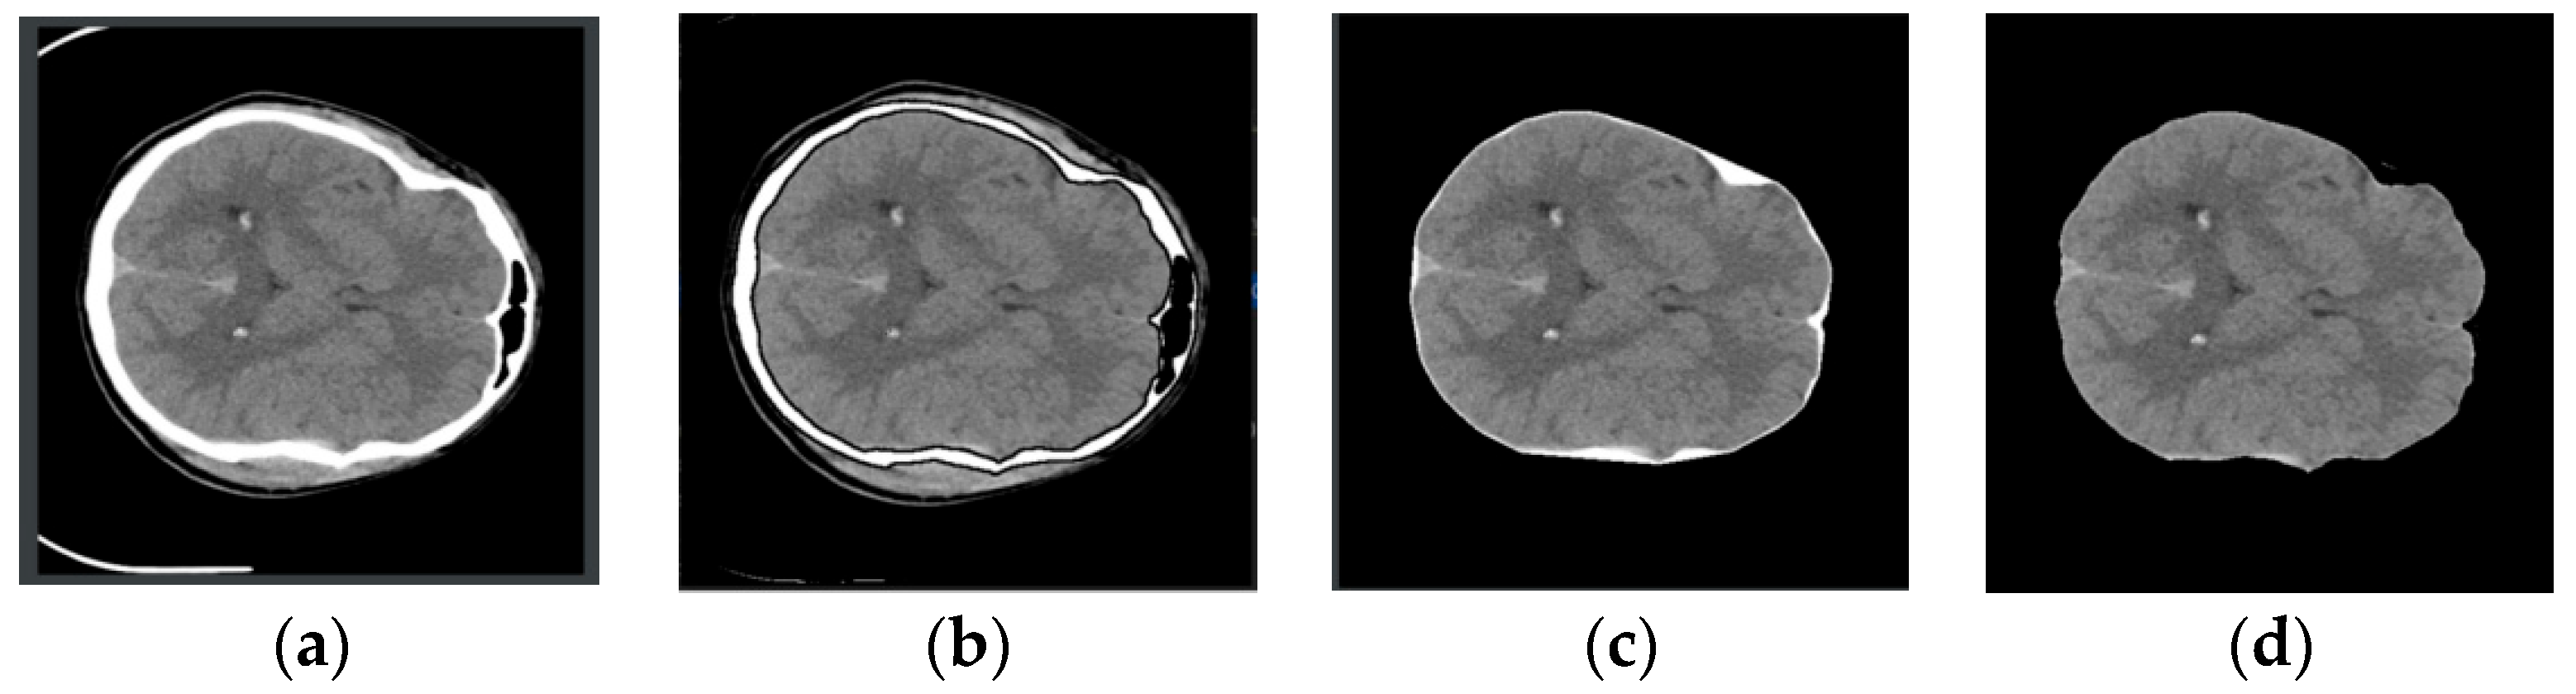

3.1. Image Preprocessing